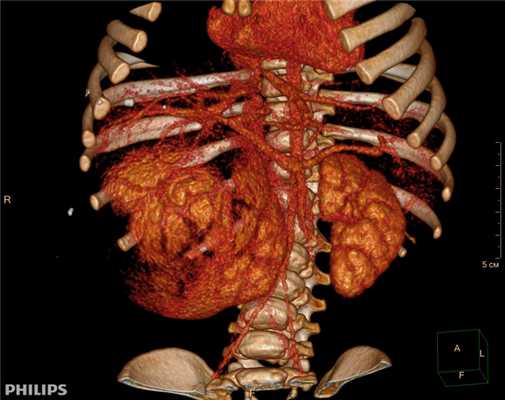

3D-реконструкции опухоли Вильмса пациентов детского отделения НМИЦ онкологии им. Н.Н. Петрова